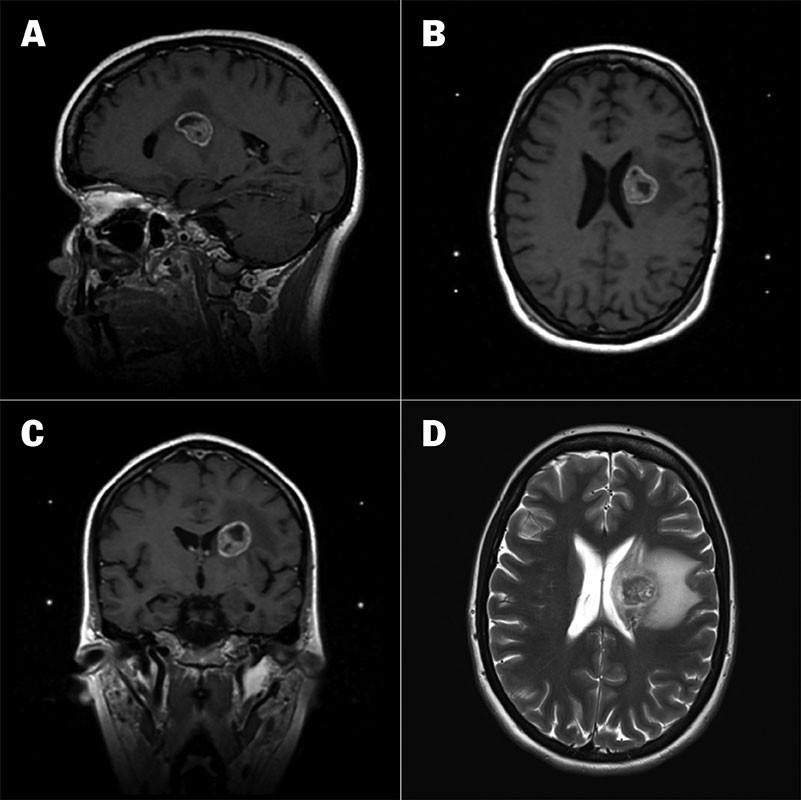

Brain CT and MRI revealed a 23 mm large expansive process and perifocal oedema in the left thalamus, exerting a mass effect on the adjacent left lateral ventricle (Figures 1a–d). A chest CT revealed a 5.6 cm tumour in the right upper lobe (Figure 2). Enlarged mediastinal paratracheal lymph nodes were observed on the right side (station 4R) in addition to enlarged paraaortic lymph nodes (station 6R).

Lung cancer with metastasis to the lymph nodes and brain was now suspected. Fine-needle aspiration cytology after bronchoscopic biopsy of lymph node 4R showed metastasis from poorly differentiated non-small cell carcinoma, confirming the diagnosis.